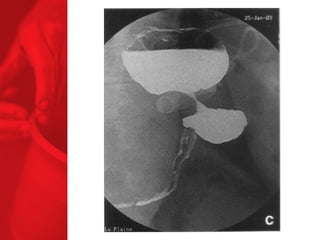

GASTRIC BYPASS Lesprocédures de malabsorption et restrictives > 56% de perte de poids excédentaire après quatre ans* > diminue le diabète de type 2 chez plus de 83 % des patients* *Christou NV, Sampalis JS, Liberman M, et al. Surgery Decreases Long-Term Mortality, Morbidity, and Health Care Use in Morbidly Obese Patients. Annals of Surgery 2004;240(3):416-424. ** Buchwald H, Avidor Y, Braunwald E, et al. Bariatric Surgery—A Systematic Review of the Literature and Meta-analysis. Journal of the American Medical Association 2004 Oct 13;292(14).

Echecs Malgré unebonne technique du CCGL, des échecs surviennent chez 15 à 20 % des patients. Les causes de reprise pondérale sont la dilatation de la poche gastrique, la dilatation de l'anastomose gastrojéjunale, l'hypertrophie des villosités du jéjunum proximal et la prise d'une alimentation avec des liquides à haute teneur en calories. Ainsi, pour les « superobèses » pathologiques (IMC > 50 kg/m2), l'intervention de référence pourrait devenir la diversion biliopancréatique.

COMMENT FONCTIONNE LECOURT-CIRCUIT GASTRIQUE ? Facteurs chirurgicaux Restriction du volume des repas Certaine malabsorption Syndrome de chasse Réduction de l'appétit Facteurs pour les patients Apport en calories Dépense en calories BILAN ENERGETIQUE = apport alimentaire dépense en énergie